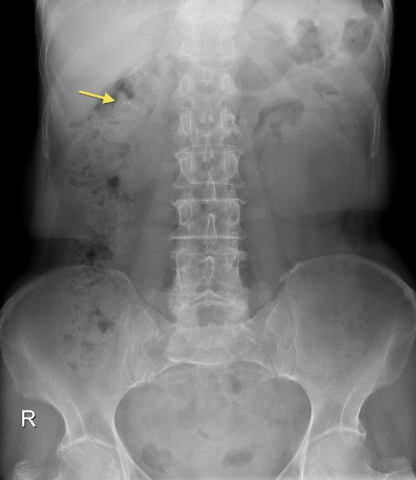

Pathology?

Calcifications